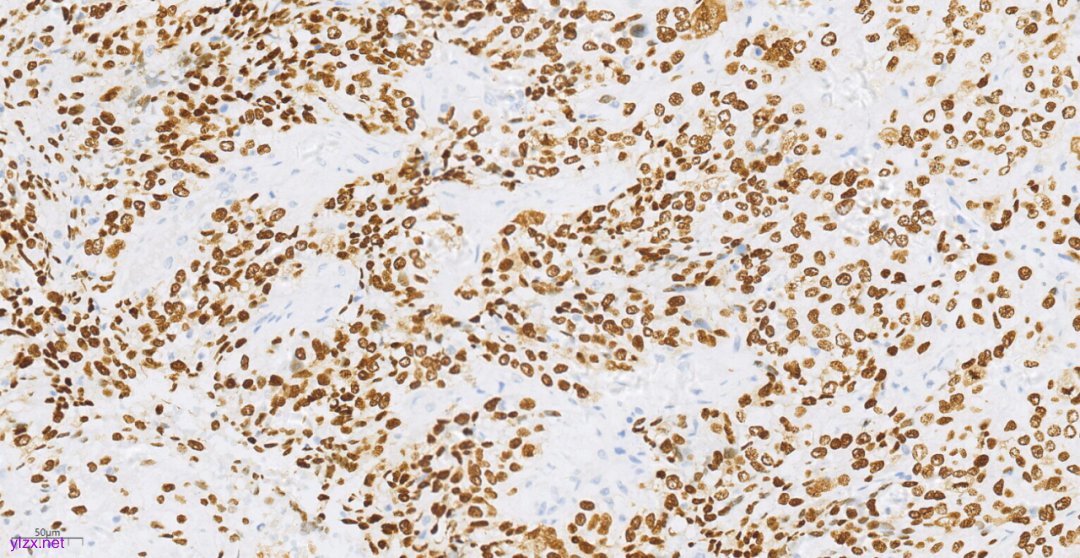

3.3免疫组化(图10-图12):

鳞癌成分CK(+),P40(+),CK5/6(+),p63(+),CK7(-),CK20(-),ER(-),PR(-),WT-1(-),Ki-67(约70%+).

图12 免疫组化示肿瘤细胞p63(+)。

免疫表型:SCC肿瘤细胞CK5/6、p63、p40阳性,ER、PR阴性。